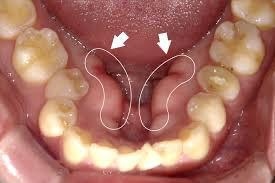

骨隆起はなに?コブみたいだけど大丈夫?